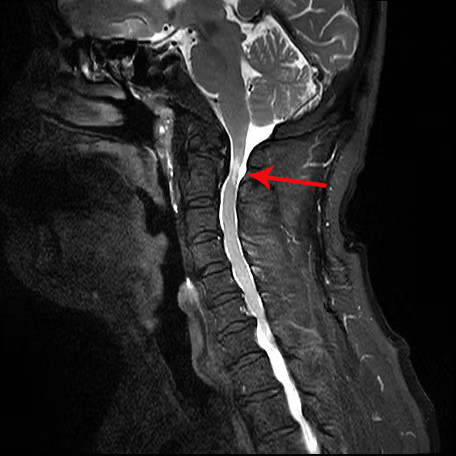

60多岁的田先生三个月前因颈痛伴四肢麻木数月来到潞河医院神经内科和脊柱外科门诊就诊。田先生曾出现摔伤后呼吸心跳骤停,当时经及时抢救得以转危为安。此次就诊,田先生及家人想寻找并拆除引起摔倒后呼吸心跳停止的“定时炸弹”。进修归来的赵鹏医生根据病史、查体、影像学检查,明确诊断:“寰枢椎不稳定(图1齿状突游离小骨)”;2.高位颈脊髓损伤(图2MRI:颈脊髓明显的水肿信号)。为了保证手术安全,赵鹏医生与已开展寰枢椎手术工作的他院专家反复讨论,并结合医院现有设备条件,从手术体位、头架使用、机器人导航操作等细节进行模拟演练,以确保手术操作按预定方案顺利进行。

箭头所示为脊髓内高信号表现